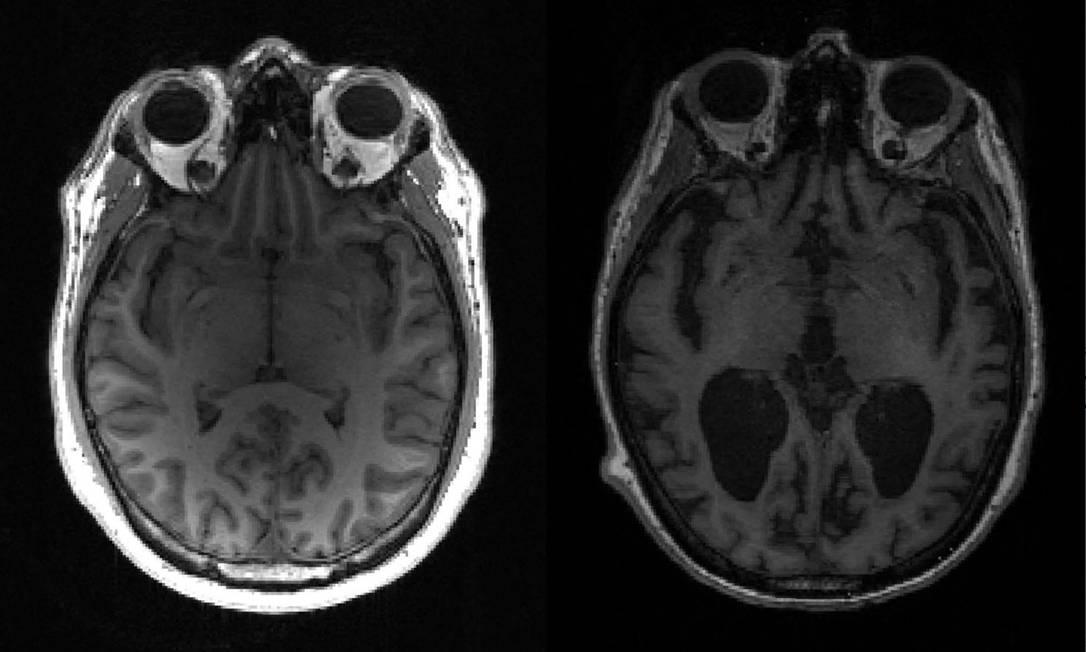

Legenda: Teste será feito com pacientes em estágios leve a moderado da doença